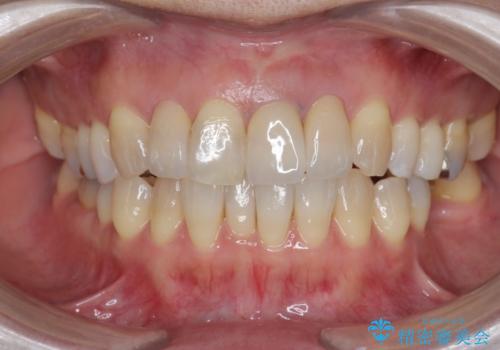

周囲の歯に調和したセラミッククラウンを作製し、審美性を大幅に向上させることができました。